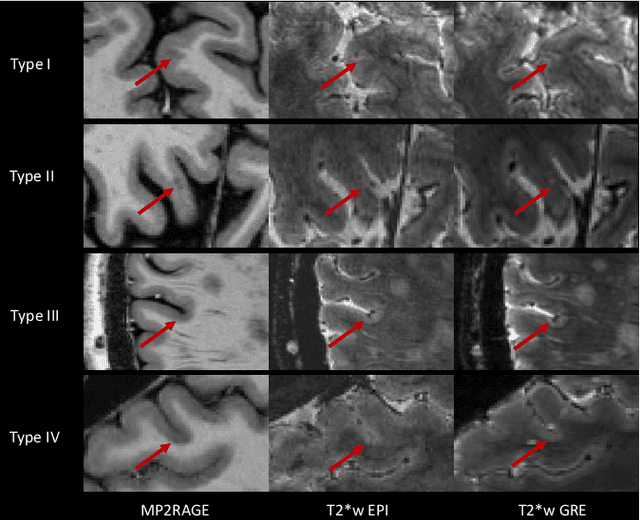

Abstract:The current multiple sclerosis (MS) diagnostic criteria lack specificity, and this may lead to misdiagnosis, which remains an issue in present-day clinical practice. In addition, conventional biomarkers only moderately correlate with MS disease progression. Recently, advanced MS lesional imaging biomarkers such as cortical lesions (CL), the central vein sign (CVS), and paramagnetic rim lesions (PRL), visible in specialized magnetic resonance imaging (MRI) sequences, have shown higher specificity in differential diagnosis. Moreover, studies have shown that CL and PRL are potential prognostic biomarkers, the former correlating with cognitive impairments and the latter with early disability progression. As machine learning-based methods have achieved extraordinary performance in the assessment of conventional imaging biomarkers, such as white matter lesion segmentation, several automated or semi-automated methods have been proposed for CL, CVS, and PRL as well. In the present review, we first introduce these advanced MS imaging biomarkers and their imaging methods. Subsequently, we describe the corresponding machine learning-based methods that were used to tackle these clinical questions, putting them into context with respect to the challenges they are still facing, including non-standardized MRI protocols, limited datasets, and moderate inter-rater variability. We conclude by presenting the current limitations that prevent their broader deployment and suggesting future research directions.